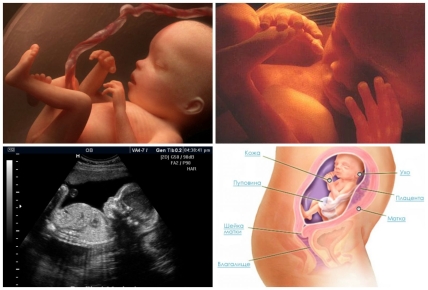

За предыдущую неделю малыш прибавил в весе и вырос, теперь его масса около 450 г., а рост около 25 см. Активный набор веса обусловлен тем, что малыш наращивает подкожный жир, а это же время в коже образовывается красноватый пигмент, а пушок лануго на голове начинает темнеть.

Внешне малыш уже похож на вполне сформированного человечка, правда совсем крохотного и пока еще неспособного к жизни вне материнского живота. Но он уже очень охотно вступает контакт, например, если слегка надавить на свой живот, то ребенок отзовется несильным толчком именно в месте надавливания.

На 23 неделе беременности дыхательная система малыша совершенствуется, и плод начинает совершать постоянные дыхательные движения, так до этого периода он это делал эпизодически и с перерывами. Во время дыхания в легкие попадает значительное количество околоплодных вод, что способствует их развитию и созреванию – альвеолы расширяются и сужаются точно так же, как и при вдыхании кислорода. В альвеолах образуется специальное вещество – сурфактант, которое после рождения ребенка на свет обеспечат заполнение дыхательных мешочков воздухом, и предотвратит их спадание.

Половые органы (у мальчиков – мошонка, у девочек – яичники) хорошо развиты. Матка поднялась на 3 см над пупком. Рост ребенка 23-25 см, вес 550 г, как длинный кукурузный початок».

Также на 23 неделе беременной женщине предстоит сдать общий анализ крови и анализ мочи, если это не было сделано на 22 неделе, и пройти УЗИ. Помимо оценки состояния плаценты, околоплодных вод, наличия или отсутствия пороков развития плода, сейчас УЗИ уже наверняка может показать пол малыша.